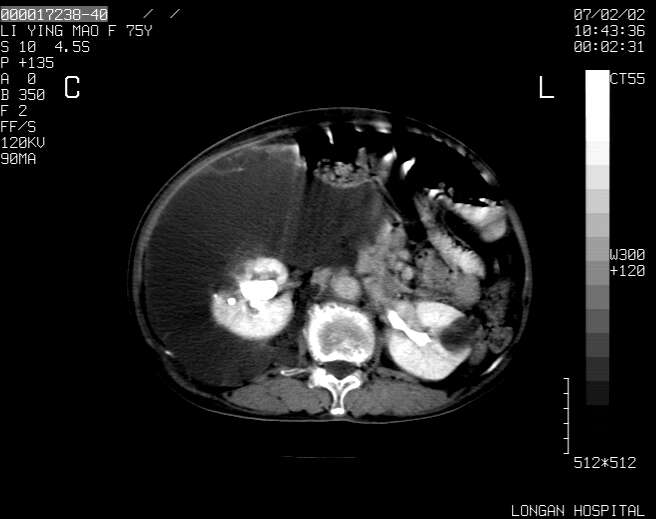

以下是引用dyqct在2007-2-10 8:53:00的发言:[br]考虑:1、肝脏多发囊肿[br] 2、左肾囊肿,右肾多发结石并积水。[br] 3、右胸少量积液。[br] 4、右肾周包裹性积液或淋巴管瘤(有见缝就钻的征象、薄隔、小结节状钙化)?[br] 5、腰椎动脉瘤样骨囊肿?[br] [br] [br]